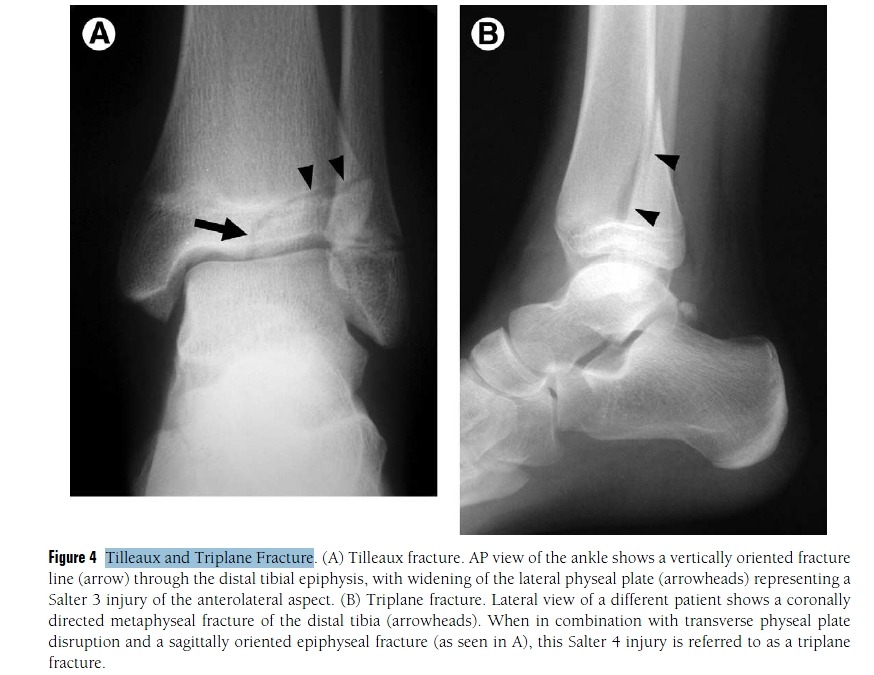

Calcaneonavicular Coalition

Figure 19 Coalition.

(A) Calcaneonavicular coalition. Lateral view of the ankle shows a talar beak (arrow), which is often

associated with coalition. Note the “anteater sign,” in which the anterior calcaneal process (arrowheads) continues into

the navicular bone, caused by a coalition.

(B) Calcaneonavicular coalition. Lateral oblique view of the foot of the same patient as (A) optimally depicts the site of calcaneonavicular coalition (arrows).

(C) Subtalar coalition. Lateral view of the ankle shows a talar beak (arrow) and a “C sign” (arrowheads) caused by a prominent sustentaculum tali seen in the setting of subtalar coalition

(D) Subtalar coalition. Harris–Beath view of the same patient as (C) shows bone prominence at the sustentaculum tali (arrow) and lack of visualization of the middle facet compared with the posterior facet (arrowhead), which should be in the same plane.

tasal coalition에 대한 mri자료

첨부파일 MRI of Tarsal Coalition.pdf